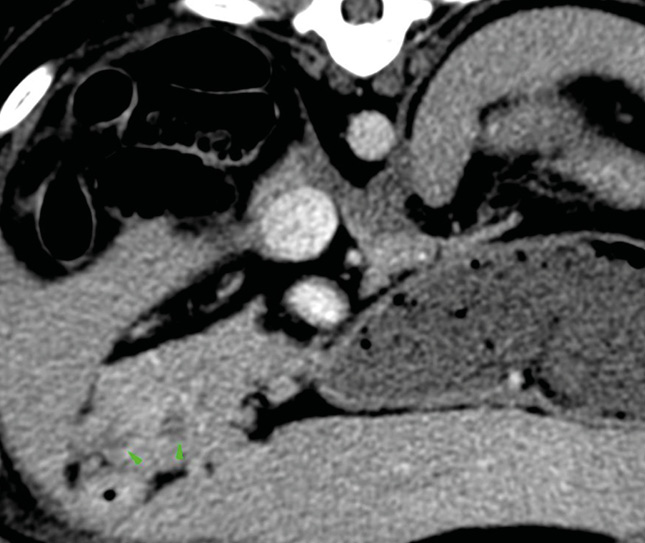

En casos de obstrucción biliar se debe considerar la duodenotomía y la colocación de un stent temporal en el colédoco, que sale al duodeno a través de la papila duonedal mayor, mientras se resuelve la compresión temporal por el absceso/inflamación (imágenes 2A y 2B). La colocación de stents de colédoco también se ha descrito en gatos.25-27 En esta especie, durante este procedimiento se debe tener cuidado de no cateterizar el conducto pancreático debido a la conexión anatómica entre el conducto pancreático y el conducto biliar común.28